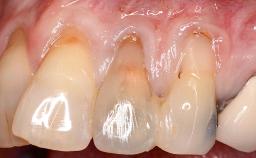

Periodontal Plastic Surgery and Prosthetic Procedures to Treat Peri-Implant Soft-Tissue Dehiscences

A 30-year-old woman was referred by her general dentist for evaluation of an esthetic complication related to previous implant treatment for congenitally missing maxillary lateral incisors. The patient’s chief complaint was the inadequate esthetic appearance of her smile. The case demonstrates the use of a combined approach to achieve optimal results. Two different flap designs - a tunnel technique and a coronally advanced flap - are employed based on the surgical objectives for the affected site.

Soft Tissue Anatomy Intact Defective

Soft Tissue Contour and Volume Slightly compromised